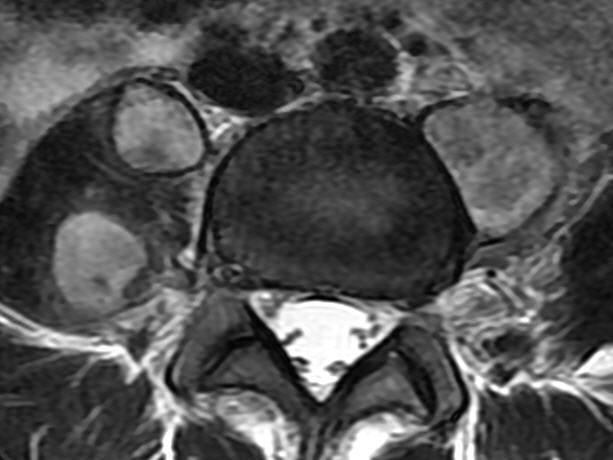

MRI

可提供腰椎管的矢状面、冠状面和轴位横断面上的影像。椎管狭窄以T2加权像显示较好,脑脊液为高信号,产生所谓“脊髓造影”的效果,而骨质增生,骨赘、间盘均为低信号,能清晰地显示椎管狭窄,以及对脊髓的压迫情况。但对肥大的黄韧带、骨质增生等的判断则不如较高清晰度CT扫描。

腰椎管狭窄MRI表现。